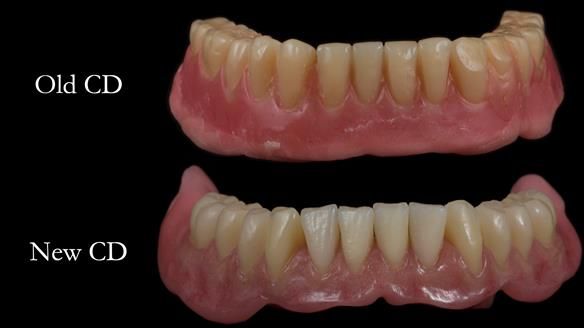

Welcome to Newsletter 62. In this edition, I walk through the process of removing 5 upper anterior teeth, adding to an existing upper RPD, followed by creating and fitting metal based complete dentures for Rafique, a 71 year old man.

Inadequate upper and lower dentures – thickened with reline material. Almost unwearable.

The detailed clinical situation and treatment process are outlined below, with clinical work provided by me and technical work by Rowan Garstang. The treatment spanned 12 months, involving removing 5 upper anterior teeth, adding to an existing upper RPD, followed by creating and fitting metal based complete dentures.